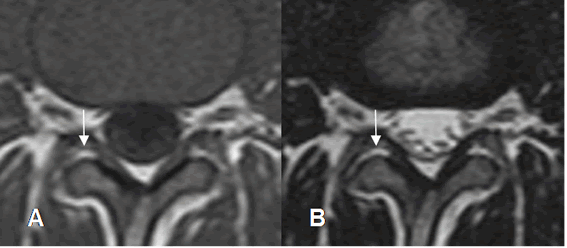

Fig 22. Articulaciones intervertebrales normales.

A: RM axial en T1 y B: RM axial en T2. Articulaciones intervertebrales normales con espacio ocupado por grasa, hiperintensa en ambas secuencias.